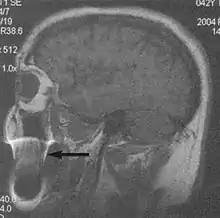

Motion artifacts

A motion artifact is one of the most common artifacts in MR imaging.[2] Motion can cause either ghost images or diffuse image noise in the phase-encoding direction. The reason for mainly affecting data sampling in the phase-encoding direction is the significant difference in the time of acquisition in the frequency- and phase-encoding directions.[1] Frequency-encoding sampling in all the rows of the matrix (128, 256 or 512) takes place during a single echo (milliseconds). Phase-encoded sampling takes several seconds, or even minutes, owing to the collection of all the k-space lines to enable Fourier analysis. Major physiological movements are of millisecond to seconds duration and thus too slow to affect frequency-encoded sampling, but they have a pronounced effect in the phase-encoding direction. Periodic movements such as cardiac movement and blood vessel or CSF pulsation cause ghost images, while non-periodic movement causes diffuse image noise (Fig. 1). Ghost image intensity increases with amplitude of movement and the signal intensity from the moving tissue. Several methods can be used to reduce motion artifacts, including patient immobilisation, cardiac and respiratory gating, signal suppression of the tissue causing the artifact, choosing the shorter dimension of the matrix as the phase-encoding direction, view-ordering or phase-reordering methods and swapping phase and frequency-encoding directions to move the artifact out of the field of interest.[1]